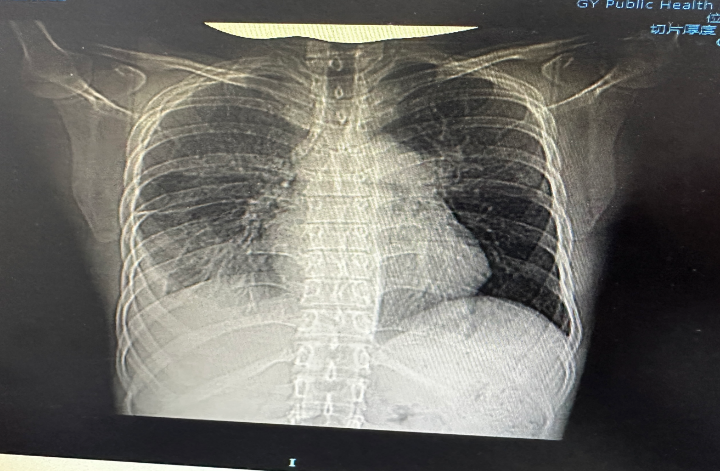

患者術(shù)前術(shù)后影像對(duì)比

病人收入外三科后,石頭主任及周波副主任醫(yī)師查看患者體征及CT結(jié)果,CT顯示:雙肺上葉及左肺下葉散在少量斑點(diǎn)灶,右肺下葉滲出伴右下胸膜肥厚及右側(cè)少量包裹性積液,考慮繼發(fā)性肺結(jié)核伴結(jié)核性胸膜炎的可能性大,胸9椎體骨質(zhì)破壞,椎旁軟組織增厚??紤]患者右側(cè)結(jié)核性胸膜炎病史較長,引起胸腔塌陷,胸膜增厚,胸膜板形成,手術(shù)風(fēng)險(xiǎn)極高,單一科室無法完成該手術(shù)?;颊咴谑⊥獾榷嗉裔t(yī)院就診,但都因手術(shù)風(fēng)險(xiǎn)高而沒有得到及時(shí)的救治。